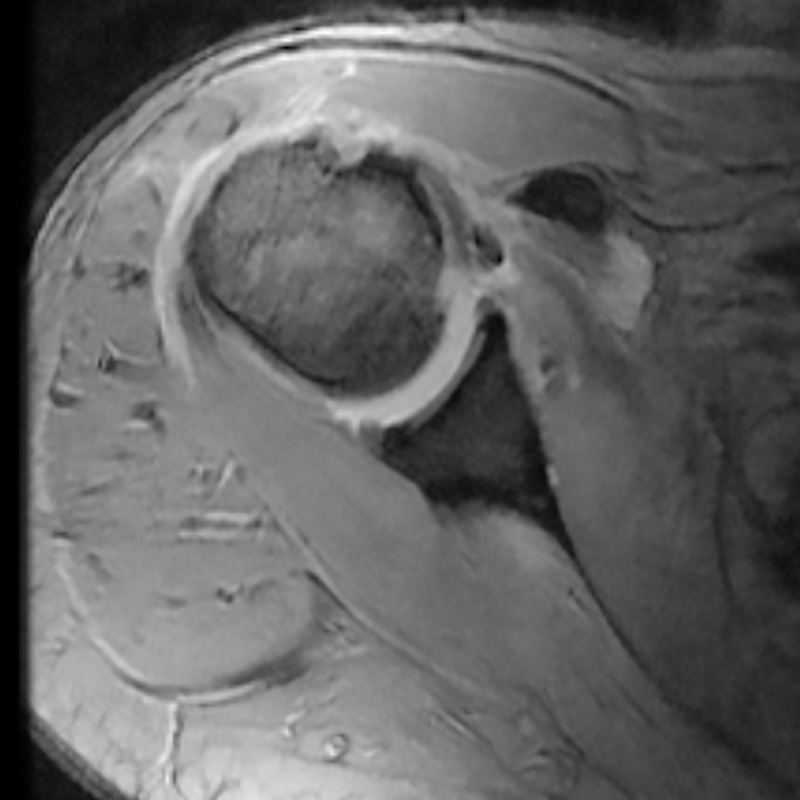

Hay que tener en cuenta que la RMN estándar y la ecografía tienen falsos negativos en las lesiones parciales, siendo la artro-RMN mucho más sensible(19,20,21,22) (Figura 1).

Figura 1. Corte axial de una resonancia magnética nuclear donde se observa una luxación del tendón de la porción larga del bíceps.